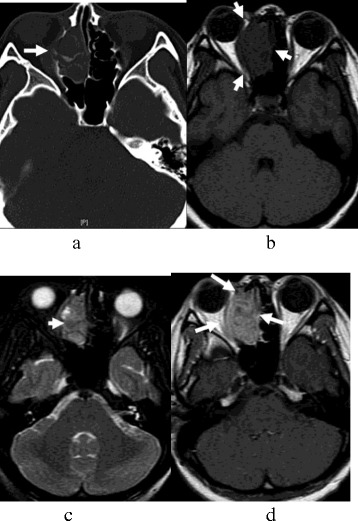

Figure 2.

SNEC of paranasal sinuses in a 53-year-old man (a-d). The tumor size was about 4.3 cm × 4.1 cm × 3.1 cm. (a) CT image showed worm-eaten bone destruction in the right ethmoidal sinus and fossa orbitalis; however, bone contours still could be seen. (b) T1-weighted MR image demonstrated isointensity. (c) T2-weighted MR image demonstrated isointense mixture. (d) Contrast-enhanced T1-weighted MR image demonstrated a mild heterogeneous enhancement mass, which showed involvement of the pharyngonasal cavity and fossa orbitalis.